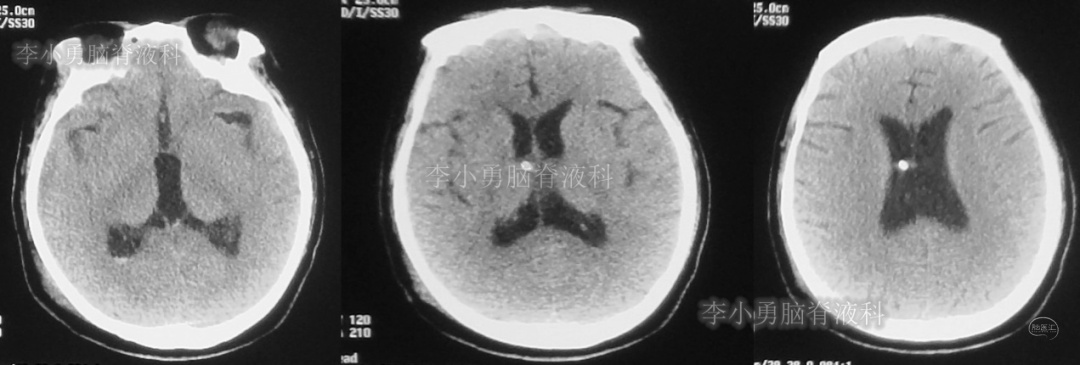

次日,即2018年11月11日,患者第2次到给予脑室腹腔分流术的医院,复查头颅CT(图-5)见脑积水仍严重。

图-5:2018年11月11日头颅CT

但第2次调压后2周,即2018年11月28日,再次到当地的第1家医院复查头颅CT(图-6)见脑积水缓解。

图-6:2018年11月28日头颅CT